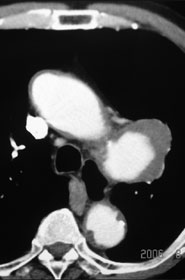

胸部CT検査

【治療計画】

Gore社TAG stent留置術

平成18年5月検診にて胸部大動脈瘤を指摘。

7月当院紹介受診。

65歳 胃癌 → EMR

高血圧(+) 糖尿病(−) 喫煙歴(−)